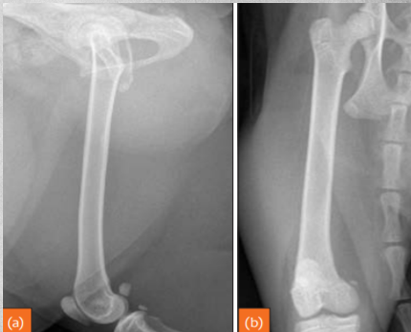

identify

Hyperthrophic osteopathy in dogs Primary neoplasia in thorax or abdominal cavity that affects long bones. Makes them "hairy".